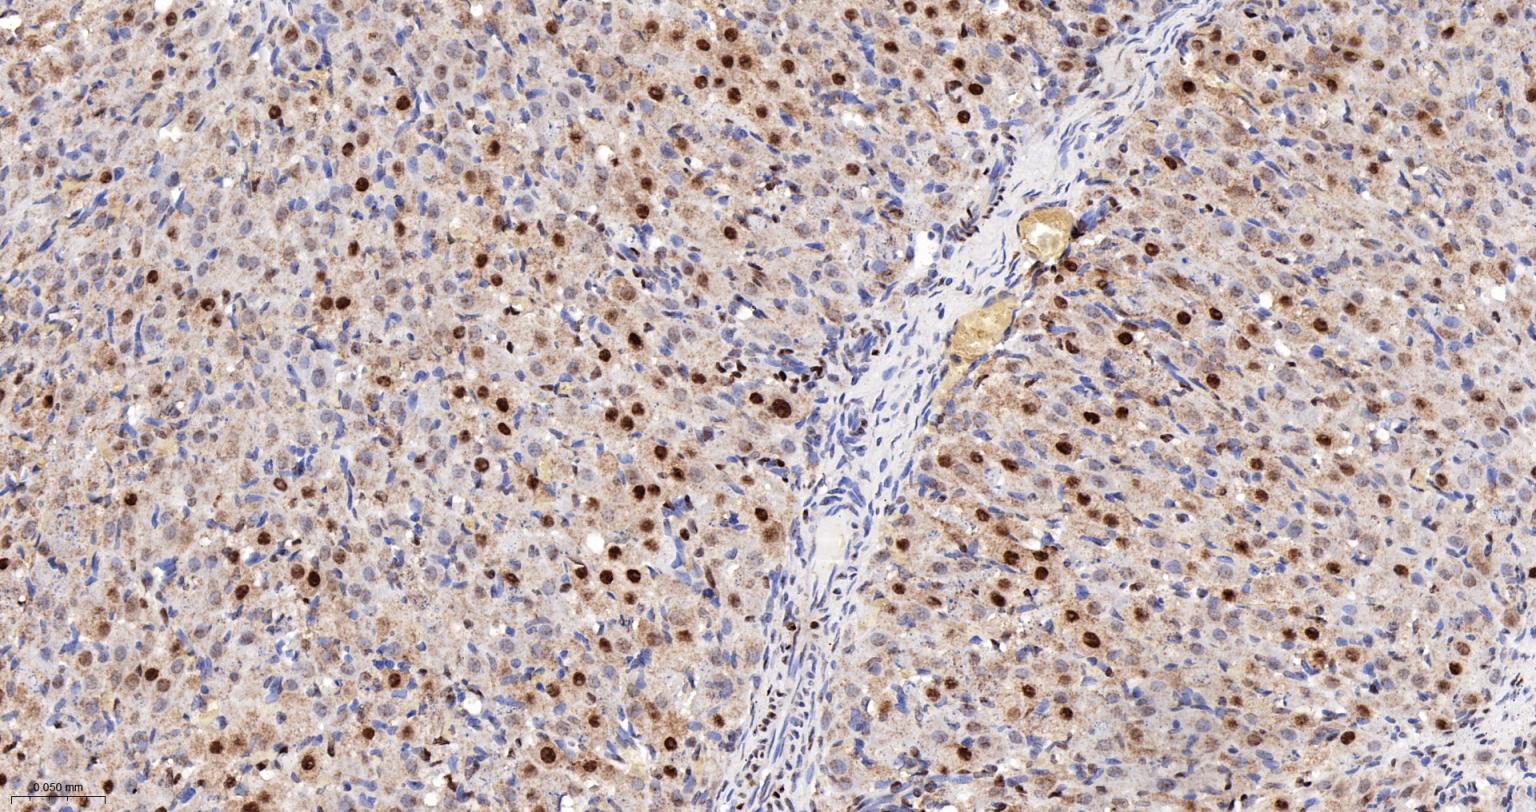

Paraformaldehyde-fixed, paraffin embedded Human Ovary; Antigen retrieval by boiling in sodium citrate buffer (pH6.0) for 15 min; The section was incubated with COUP-TF1 Monoclonal Antibody, Unconjugated (bsm-61615R) at 1:200 overnight at 4°C, followed by conjugation to the bs-0295G-HRP and DAB (C-0010) staining.